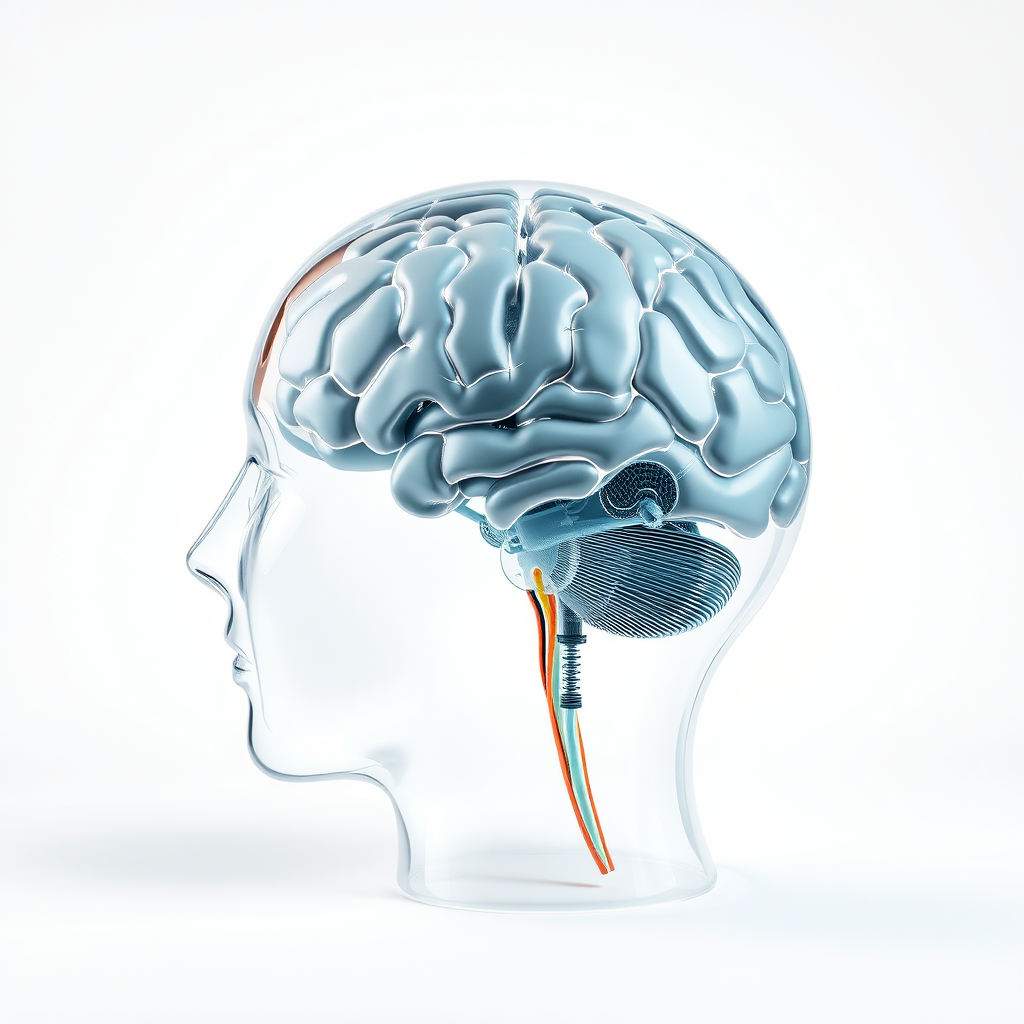

Um neuropsicólogo é um profissional que atua nessa área, investigando a conexão entre o cérebro e o comportamento humano.

Este campo é essencial para a avaliação, diagnóstico e tratamento de condições que afetam a saúde mental e cognitiva.

A reabilitação neuropsicológica visa restaurar funções cognitivas comprometidas.

A estimulação cognitiva foca em melhorar habilidades específicas, como memória e atenção.

O neuropsicólogo desempenha um papel crucial no tratamento de transtornos neurocognitivos.

Este profissional é especializado em entender como as funções cerebrais afetam o comportamento e as emoções.